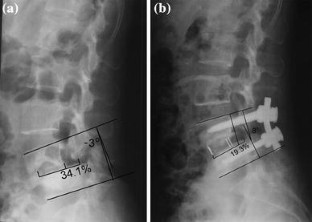

Fig. 2